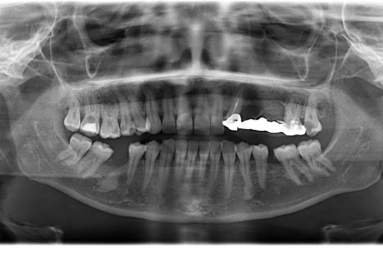

Initial situation: the patient had a an incorrect bridge for five years in the left maxillary area, this caused the extraction of the posterior tooth that was sustaining the bridge together with the wisdom tooth then three implants were inserted in the maxillary bone.

After the osseointegration of the implants three porcelain and zirconium crowns were made. At the same time full ceramic crowns were made for the left canine and the two right premolars, which had deep cavities and needed root canal treatment.